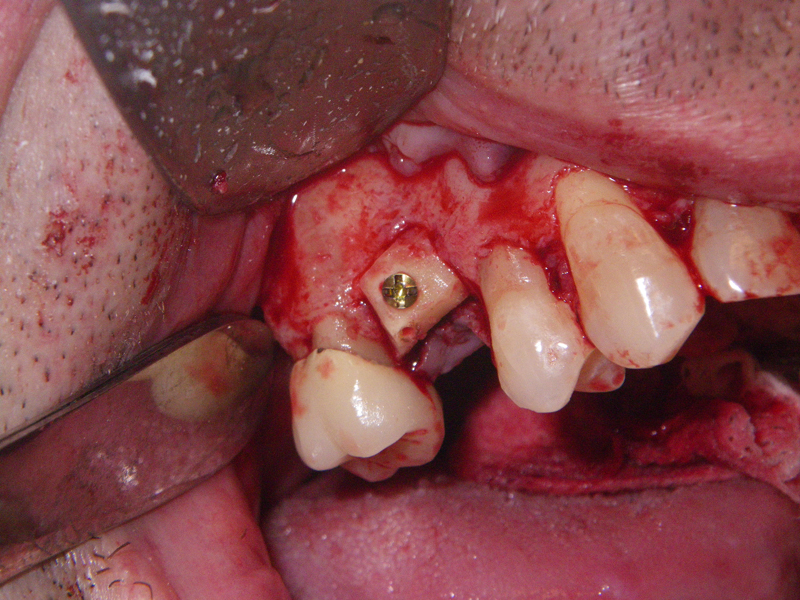

- Stage I: Implant placement/Sealing Screw

- Alveolar Ridge Augmentation

- Blockgraft

- Socket presentation